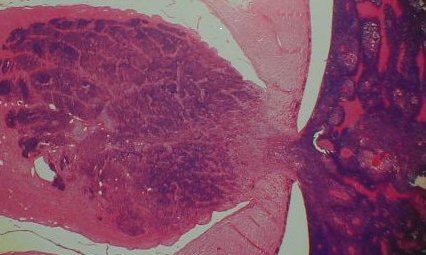

An endophytic retinoblastoma. The tumour grows

into the vitreal cavity. (In exophytic type, the

tumour grows into the subretinal space).

Optic nerve (O) invaded by retinoblastoma (R).

Optic nerve (left) infiltrated by retinoblastoma (right). Note the presence of retinoblastoma (dark blue) in the optic nerve substance.